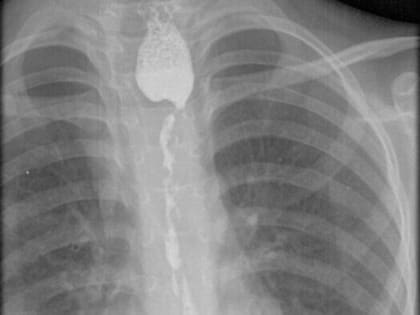

Сложнейшую операцию - колоэзофагопластику - провели хирурги Ивано-Матренинской детской клинической больницы.